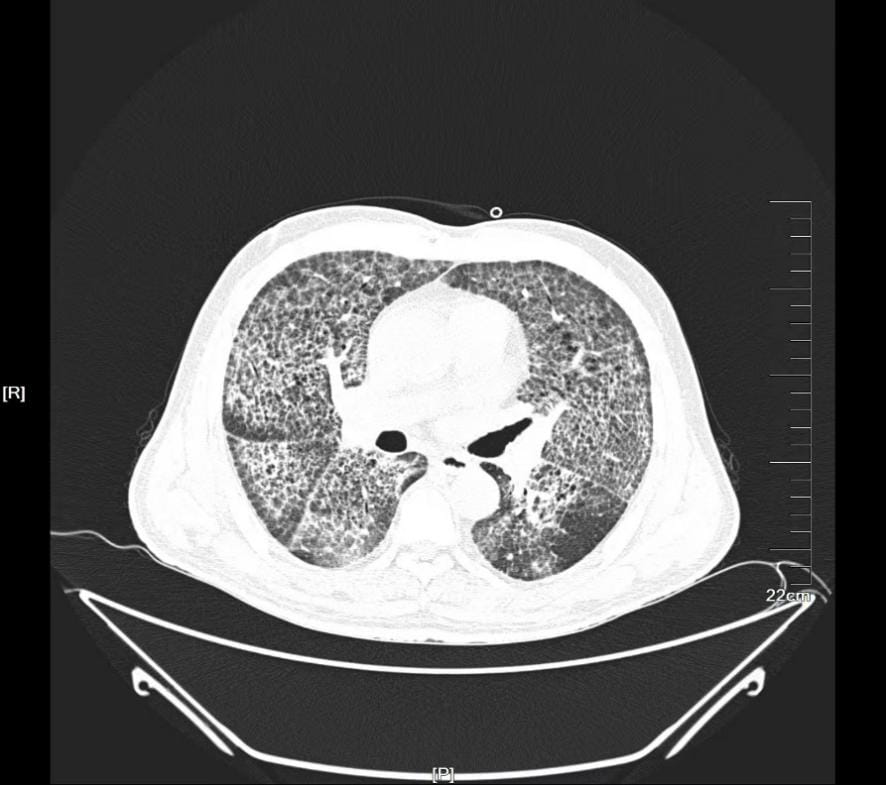

▲术前CT